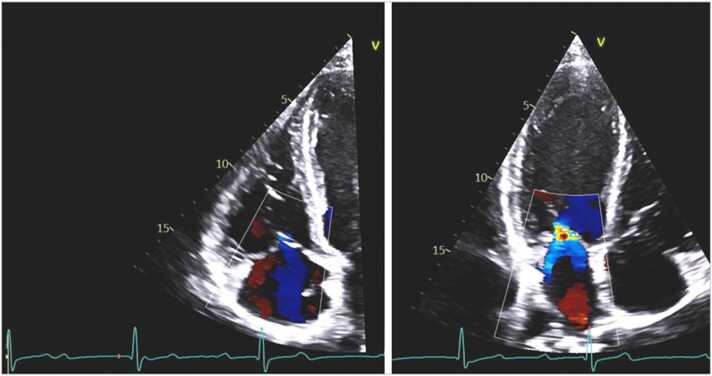

Fig. 2.

Echocardiography from apical 4-chamber views showing tricuspid regurgitation (left) and mitral regurgitation (right) during diastole. Red marker on the ECG denotes where in the cardiac cycle the image was taken.

In July 2022, a 37-year-old previously healthy male who lived and worked in northwestern Wisconsin, presented to the emergency department with two episodes of syncope without prodromal symptoms in the past 5 days. During these days, he had increasingly frequent episodes of dizziness and near-syncope. He also reported fever, chills, muscle aches, and bilateral lower extremity erythematous rash that had developed 3 weeks earlier that had resolved by the time of presentation. The patient reported removing several ticks from his left thigh and groin in April and May of 2022. SARS-CoV-2 tests were negative for active infection and he had no history of recent travel. An initial electrocardiogram (ECG) revealed complete heart block with a heart rate of 55 bpm (Fig. 1), so a temporary pacemaker was urgently inserted. Laboratory testing was positive for B. burgdorferi IgM and IgG antibodies on enzyme-linked immunosorbent assay (ELISA) screen and confirmatory western blot. Based on these data, Lyme carditis was diagnosed and he was started on intravenous ceftriaxone. An echocardiogram showed diastolic tricuspid and mitral regurgitation (Fig. 2). After 9 days the complete heart block resolved. Follow up ECG on day 10 showed first degree atrioventricular (AV) node block with a PR interval of 280 ms and a heart rate of 64 bpm (Fig. 3). The patient was then transitioned to oral doxycycline 100 mg PO BID to complete total 4-week course of antimicrobials and was discharged Fig. 4.

Laboratory tests are helpful to support the diagnosis, even if not required in patients with potential tick exposure in a Lyme disease endemic area with history of one or more skin lesions compatible with EM [18]. During the early disseminated phase, most patients present with IgM and IgG seropositivity against B. burgdorferi [8]. The most frequent assays used are ELISA and Western blotting [4]. In addition, 12-lead ECG and telemetry should be performed in cases with high clinical suspicion of Lyme carditis and real-time ambulatory cardiac telemetry may also be particularly useful for such patients [18]. Other tests like echocardiography and chest radiography are useful for evaluation of heart size, heart function, and the presence of pericardial effusion and pulmonary congestion [5], [9], [12]. Most cases of Lyme carditis exhibit structural and functional cardiac abnormalities that are mild and transient. In patients with AV block, diastolic mitral and tricuspid regurgitation due to dissociation of atrial and ventricular systole are often detected [19], [20] as in this case. Current guidelines do not recommend routine endomyocardial biopsy for diagnosis given the potential focality of myocarditis and the high risk of the procedure [5], although it can be considered in specific cases [21].